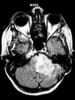

Current imaging techniques, including CT scanning and MRI (see the image below), make inferences about the level of obstruction, depending on the presence or absence of ventriculomegaly, especially fourth ventricle dilatation. Fourth ventricle dilatation implies obstruction distally, usually at the level of the subarachnoid space. A small fourth ventricle suggests obstruction proximal to the fourth ventricle. [2, 3]

Coronal magnetic resonance image shows a colloid cyst (arrow) in the roof of the third ventricle. The patient has mild hydrocephalus.